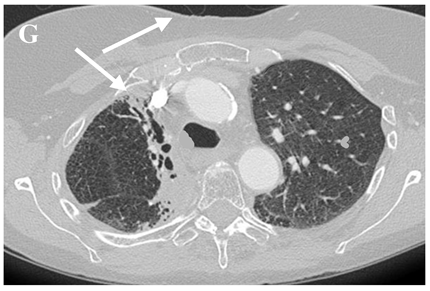

Even though X-ray is non-specific to pneumonitis, it is usually the first investigation performed. During the early phases, the most common finding on chest radiograph is perivascular haziness which frequently progresses to alveolar opacities [39]. Chest radiographs can show ground-glass opacity and/or consolidation in the radiation port. Consolidation usually has a nodular appearance but can be more confluent/lobar along with the irradiated port. Findings can be seen outside the radiation port as well. Some uncommon findings are ipsilateral pleural effusion with or without adjacent atelectasis [66]. Chest radiograph can also show bilateral interstitial infiltrates mimicking heart failure or acute respiratory distress syndrome (ARDS) [69,70]. All irradiated patients usually have some degree of abnormalities in the X-rays. Some fail to show any radiographic evidence of lung injury with pneumonitis. Early features exhibiting mild opacification of vascular markings are common, with later stages showing dense opacities. A radiographic straight-line effect may indicate the direction of the radiation port along the lines of pneumonitis [39,71] (Figure 1).

Figure 1.

Chest X-ray showing radiation pneumonitis Image 1—Frontal chest X-ray showing left upper lobe mass (arrow), the patient also had a right internal jugular port placed. Image 2—Post radiation treatment frontal chest X-ray showing increasing alveolar and interstitial opacities in the left upper lobe and in the left lower lobe in a patient suspected of radiation pneumonitis.